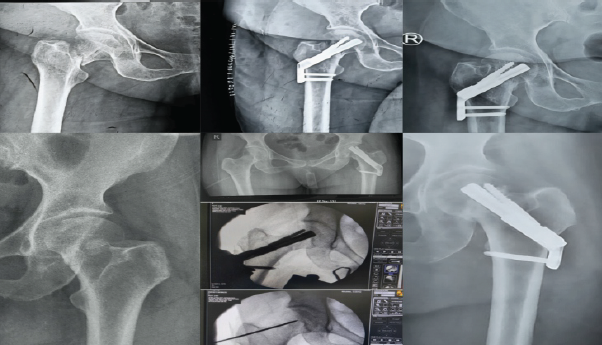

A 24-year-old male sustained a high-energy injury with multiple pelvic fractures in addition to a displaced Garden’s type IV, Pauwel’s type III femoral neck fracture. Mild traction and valgus fixation with compression were achieved using the FNS, with adequate positioning of the blade and anti-rotation screw and bi-cortical distal locking. The patient was lost to follow-up as he was a native of West Bengal. However, we established contact with the patient after 12 months and his latest X-Rays showed that the fracture had united, but by 16 months AVN of the femoral head with secondary degenerative changes developed (Fig. 3). The displacement, comminution, high-energy mechanism, and possible early return to weight-bearing may have contributed to this complication, despite good implant placement and good bone quality.

Figure 3: (Case 4) Top right: Pre-operative 3D computed tomography image showing supero-postero-lateral neck comminution; Centre-right: Immediate post-operative AP radiograph; bottom row: intraoperative C-arm images; Top left: 16 months post-operative radiographs showing fracture union and osteoarthritis hip changes secondary to AVN

Case 5

A 35-year-old male with intellectual disability sustained a displaced Garden’s type IV, Pauwel’s type II fracture. Fixation was performed with the FNS, but with only a single unicortical distal locking screw at the level of the cancellous lesser trochanter, and the anti-rotation screw locking mechanism failed, leading to backout. By 15 months, radiographs showed radiolucency and reactive bone formation around the implant, though infection was excluded clinically and with laboratory investigations. The radiographs also revealed generalized osteopenia with thinned out femoral diaphyseal cortices. A Bone Mineral Density scan was done which also revealed osteopenia (T-score – 1.8) (Fig. 4). Hence, factors that might have contributed include poor bone quality, mechanical insufficiency due to unicortical fixation, and possible abnormal femoral version and early weight-bearing on the patient’s side. The patient is now being counseled to undergo a total hip replacement.

Figure 4: Top left: Pre-operative radiographs of Case 5; Bottom row: immediate post-operative radiographs; top right: follow-up radiographs at 15 months showing fixation failure, non-union, and screw backout.